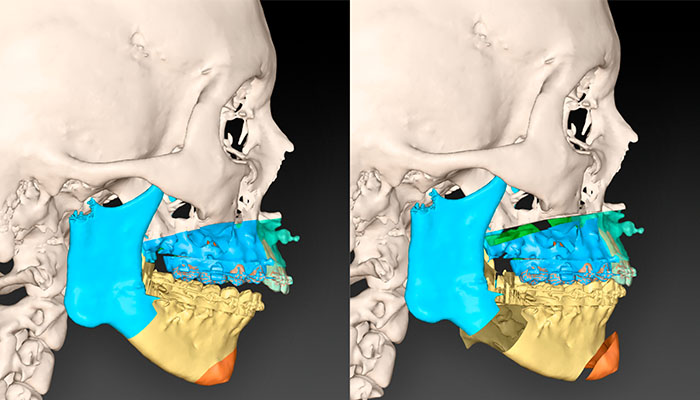

El tratamiento comienza con ortodoncia para alinear los dientes y preparar la boca para la cirugía ortognática, que se encarga de corregir la posición de los huesos faciales. Se realiza la cirugía, la ortodoncia continúa para perfeccionar la mordida y lograr un equilibrio estético y funcional.

¿Qué innovaciones hacen diferente a este tratamiento?Las técnicas modernas integran ortodoncia y cirugía para optimizar los resultados, utilizando planificación digital en 3D, procedimientos menos invasivos como corticotomías y cirugía regenerativa, además de un enfoque interdisciplinar que garantiza mayor precisión y eficacia.